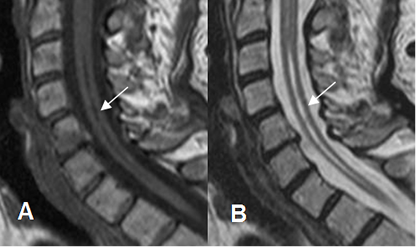

Fig 212. Siringomelia.

A: RM sagital en T1 y B: RM sagital en T2. Atrofia medular, con cavidad central hipointensa en T1 e hiperintensa en T2, que corresponde a siringomelia.